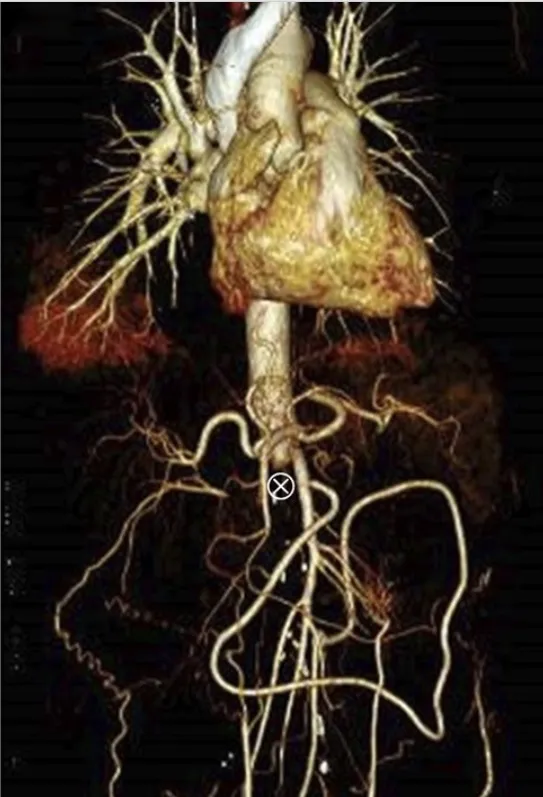

DRC indeterminada ou você esqueceu de fazer o básico? Veja tudo aqui

DRC “indeterminada” raramente é falta de diagnóstico — quase sempre é falta de método. Tempo de evolução, urina bem avaliada, USG renal e história clínica dirigida mudam conduta e evitam erros comuns na prática nefrológica.

IRA + Icterícia: Um Caso que Exige Investigação Detalhada